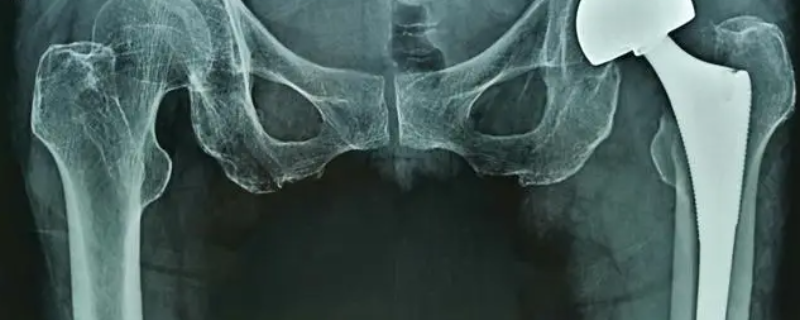

最佳答案股骨头治疗仪有用。股骨头坏死治疗仪是一种与针灸、推拿、理疗以及外科手术等不同的独特疗法,其适用于各种类型、各种原因导致的股骨头坏死的治疗。经大量临床验证表明,股骨头坏死治疗仪可以明显减轻股骨头坏死患者的疼痛,同时可以改善患者的关节活动以及步态,对坏死股骨头有一定的修复作用。